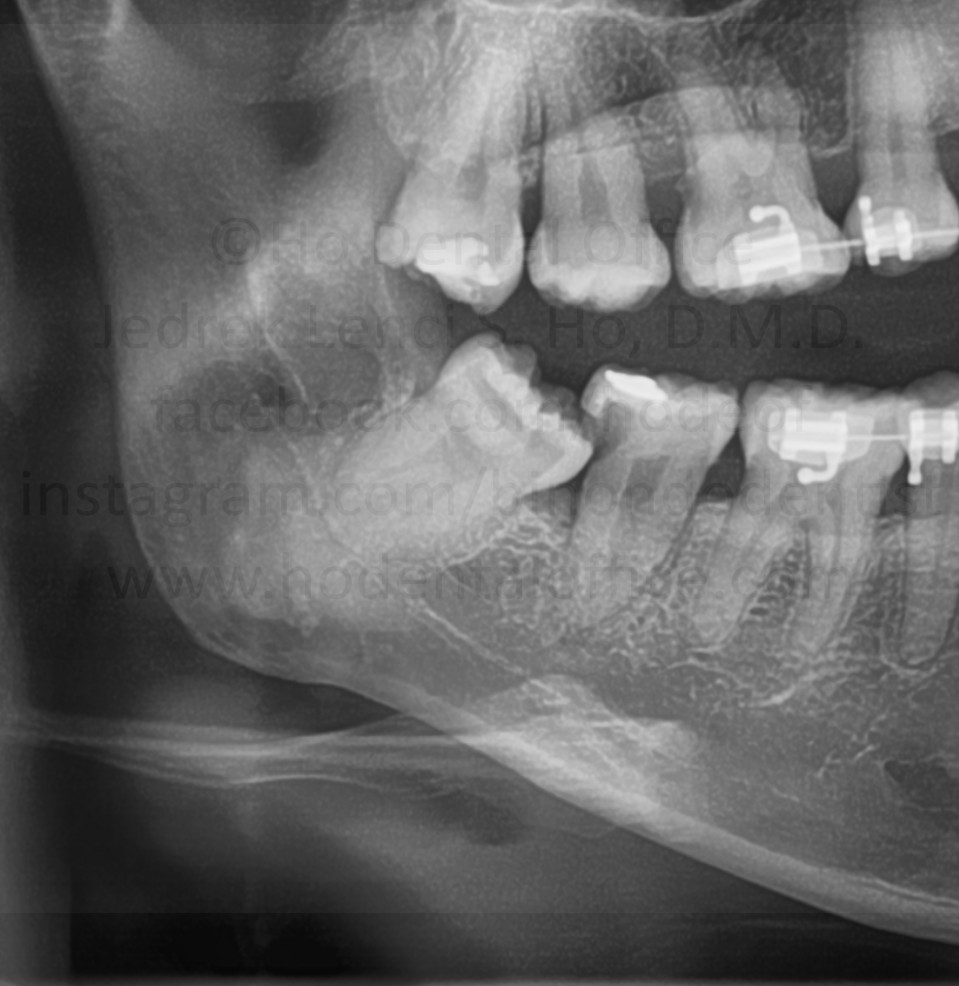

Impacted tooth are tooth that have not erupted normally in the mouth. The most common reason for it is because of a lack of space in the mouth. In most cases, they have no function in the mouth since they are out of occlusion. Therefore, it is advisable to remove them, the earlier the better, in order to avoid complications in the future.

Odontectomy is the dental procedure entailing the removal, usually with surgical intervention, of impacted tooth, usually the third molars. It is one of the most common minor oral surgical procedures in dentistry.

third molars (or wisdom tooth) - lowerupper

premolars - lowerupper

second molars - lowerupper